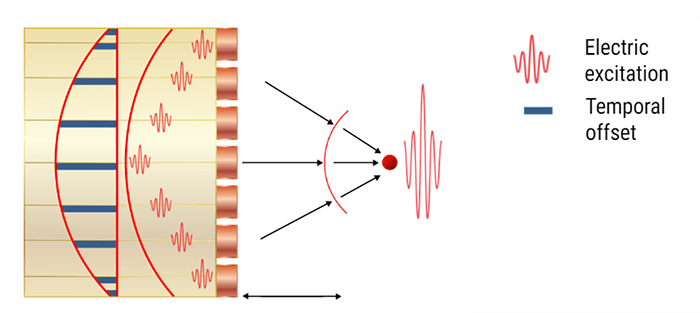

An ultrasound probe emits a pulse in response to electrical excitation. This ultrasonic pulse, transmitted to biological tissues, spreads by degrees.

The echoes are generated by reflection or scattering and propagate backward towards the probe, which operates in receiver mode immediately after the pulse is transmitted. Whenever an echo reaches the surface of the probe, an electrical signal is produced, having an amplitude proportional to that of the echo.

If we consider that an ultrasound wave propagates in the soft tissues at a constant mean speed c, the time t (echo flight time) that elapses between the emission and the reception of an echo, corresponds to the duration of a round trip to the target which is expressed simply by the fundamental relationship of ultrasound: ct = 2z, where c is the ultrasound speed, t is the time of propagation, and z is the penetration distance.

Electronic Focusing and Beam-steering

Moving on to the electronic scanning technique, a subset of piezoelectric elements work together to produce the focused beam. Each of the transducers is excited with time offsets. The combination of several focal lengths at the emission improves the quality of the image.